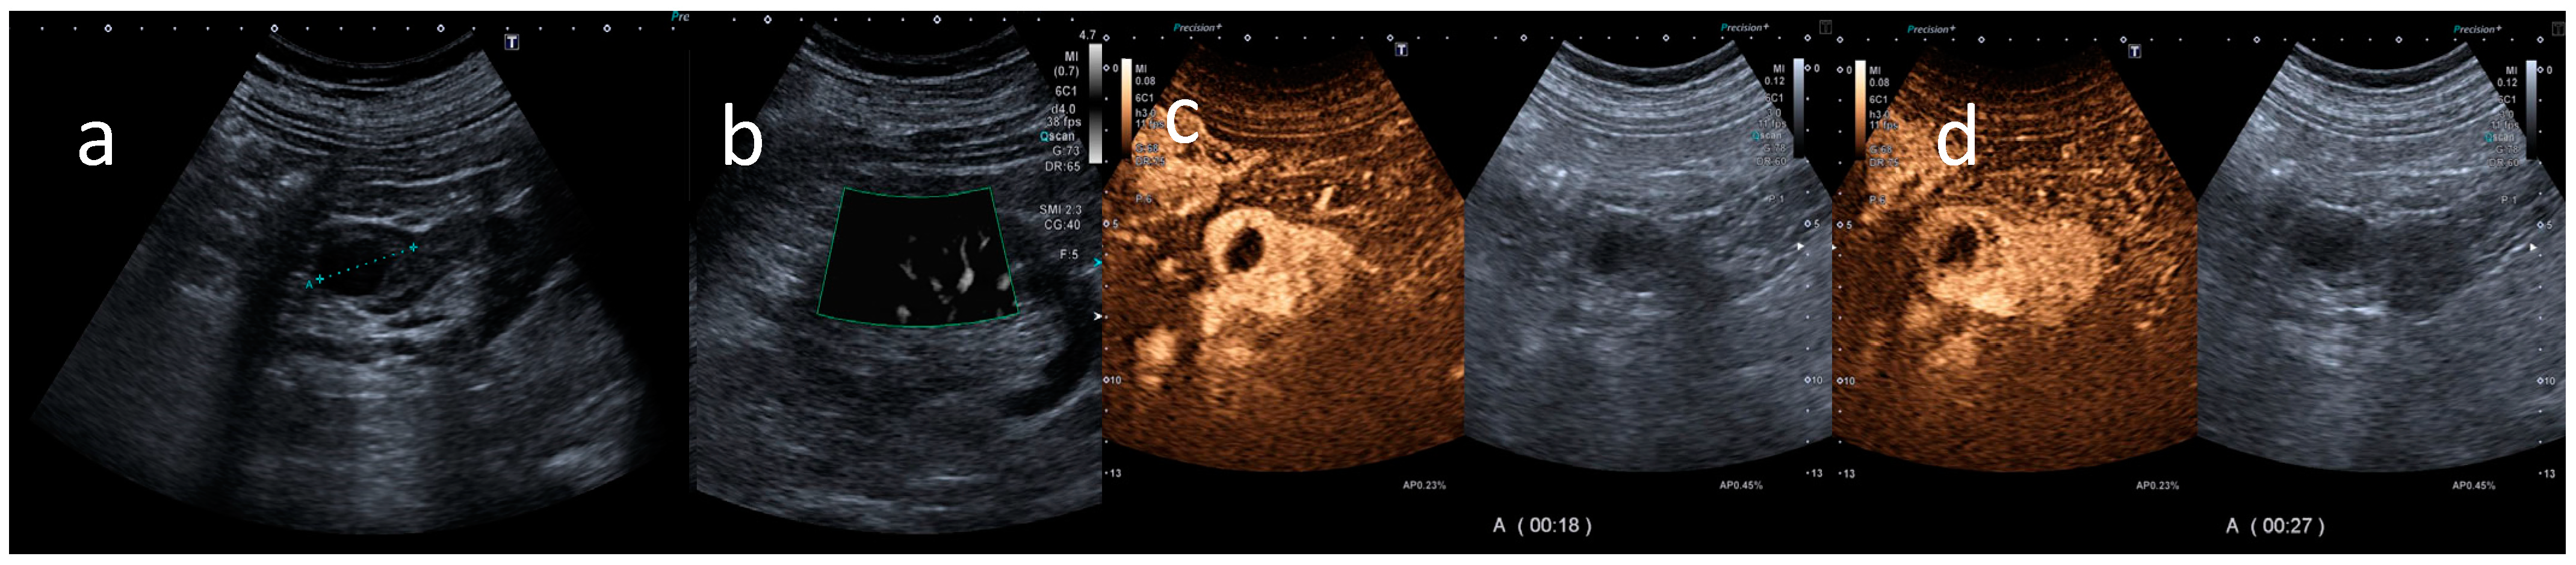

All the CEUS examinations were performed using a Canon Aplio a550 ultrasound machine (Canon Europe, Amstelveen, The Netherlands). Gray-scale B-mode ultrasound was employed for kidney lesion detection, kidney size assessment, and evaluation of echogenicity and homogeneity using a convex array transducer. The kidney was routinely examined in modified longitudinal and transverse planes and, if necessary, in deep inspiration and with optimized scanning positions. The CEUS examinations were performed during clinical routines using high-end ultrasound systems equipped with the most up-to-date CEUS-specific protocols available at the time of the examination (Figure 1).

Figure 1.

CEUS findings. B-mode ultrasound shows a complex cystic lesion irregularly thickened (a), with intravascular signal at SMI (b). In the arterial phase, after using a contrast agent (Sonovue), the contrast-enhanced ultrasound shows a marked enhancement (c) and a rapid wash-out (d) of the wall and of solid nodular components of the wall, with an un-enhanced central core of necrosis. These findings were assessed by the radiologist as positive findings for malignant small renal mass. Final pathologic assessment confirmed this assessment, as it was diagnosed as a renal cell carcinoma with foci of necrosis.